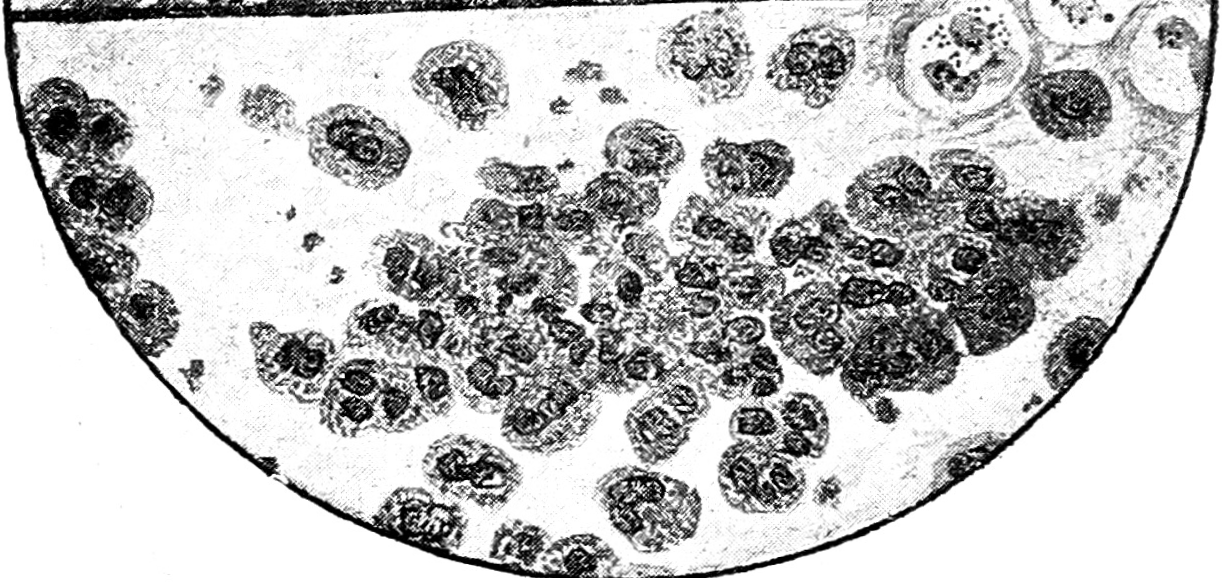

Рис. 2. Крупозная пнеймония на высоте заболевания. Фон мазка слизистый, N, большое количество МП, единичные Е.

Рис. 3. Крупозная пнеймония в стадии разрешения. Фон слизистый, N, большое количество МП, АМ.

В соответствии с макроскопическими изменениями мокроты при крупозной пнеймонии мы могли подметить строгую закономерность и в чередовании цитологических картин ее. Ржавая мокрота, обусловленная гиперэмией и пропотеванием в альвеолы плазмы крови и одновременным острым катарральным состоянием бронхов, давала под микроскопом яркую картину сплошного слизистого фона, местами перемежавшегося с очагами выпотевшего белка; на этом фоне встречалось иногда значительное количество эритроцитов, небольшое число лейкоцитов и изредка единичные моноцитоподобные клетки.

В стадии красной гепатизации число красных телец постепенно уменьшалось вплоть до полного исчезновения, зато резко увеличивалось число моноцитоподобных элементов и лейкоцитов, и появлялись AM. В дальнейшем, с переходом мокроты в гнойно-слизистую и слизистую, эритроциты совершенно исчезали, моноцитоподобные элементы постепенно уменьшались в числе, число же лейкоцитов, напротив, увеличивалось, как и число AM, а фон мокроты из сплошного становился сетчатым. Эта картина обычно держалась все время разрешения, причем AM, наростая, иногда сплошь закрывали все поле зрения. Далее мокрота постепенно теряла вышеуказанные элементы и к моменту выздоровления приобретала бронхитический вид.